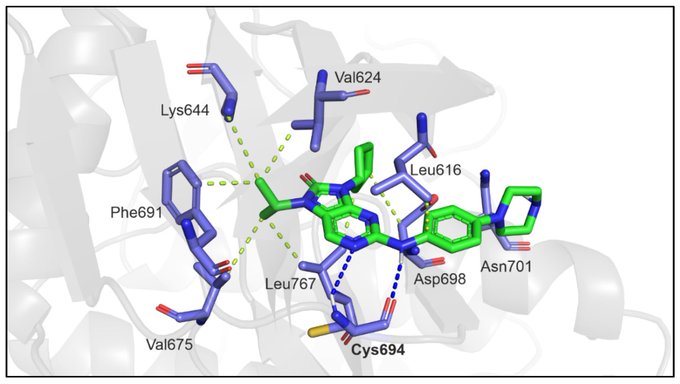

Dysregulation of Amino Acid, Lipid, and Acylpyruvate Metabolism in Idiopathic Intracranial Hypertension: A Non-targeted Case Control and Longitudinal Metabolomic Study.

Journal of Proteome Research.

2022,

22(4),

1127-1137,

ISSN: 1535-3893,

PMID: 36534069,